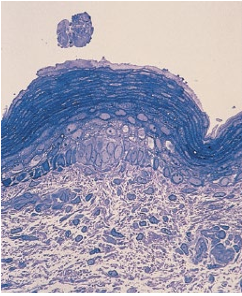

주피(periderm)는 일부 포유류와 조류에서만 볼 수 있어요

수정 후 발달 되는 피부의 가장 바깥쪽에 있는 일시적 세포층이랍니다

주피 세포가 점진적인 발달 단계를 거쳐서 형태학적으로 변화해요

주피는 태아와 양수사이에 존재함으로써 양쪽의 물질 이동에 관여하게 됩니다